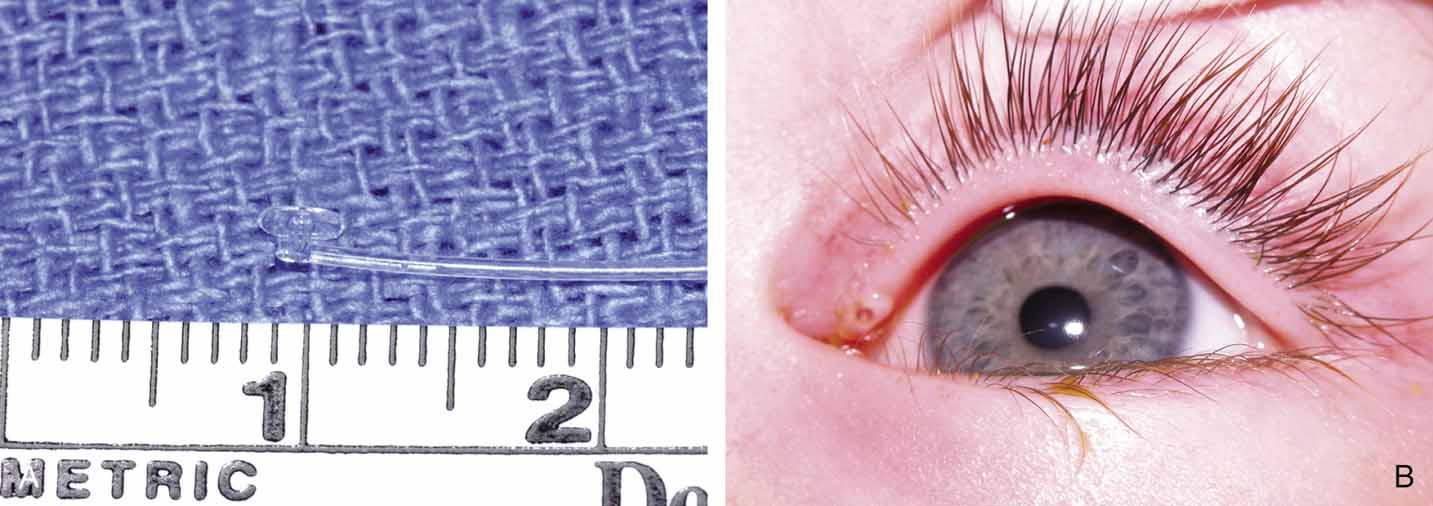

Fig. 25 A and B. Ritleng probe with hollow lumen and stylette used while passing the probe. A

slit exits along the side to remove prolene lead attached to Silastic

tubing distally.

Fig. 25 A and B. Ritleng probe with hollow lumen and stylette used while passing the probe. A

slit exits along the side to remove prolene lead attached to Silastic

tubing distally.

As for the monocanalicular stents, our preference is to use the Ritleng

probe for passage. This hollow probe has a directed groove at the distal

tip (Fig. 25A and 25B). The prolene portion on the Silastic tubing is fed down the probe

and recovered from the nose (Fig. 26). Sometimes the directional groove will lead the prolene portion

directly out the nostril. It is helpful to feed a majority of the prolene

down the probe to facilitate distal recovery. The Ritleng hook, Crawford

hook, or myringotomy forceps can be utilized to retrieve the prolene

portion from the nose. If any trouble is encountered retrieving

the prolene feeder, the surgeon should feel for the Ritleng probe and

hook it. Once the hook is around the probe, the probe should be rotated 180 degrees

because this will position the distal opening of the probe

posteriorly. In addition, the probe should be slightly withdrawn. The

hook will engage the prolene feeder when the hook is pulled anteriorly. It

is important to note that the prolene thread has two portions, a

light blue section and a dark blue section. The darker portion has

a thicker diameter. When all the dark prolene has been inserted down the

probe, the light blue, thinner portion should be passed outside the

slit on the side of the probe. Simultaneously, the probe should be removed

proximally from the nasolacrimal system. |